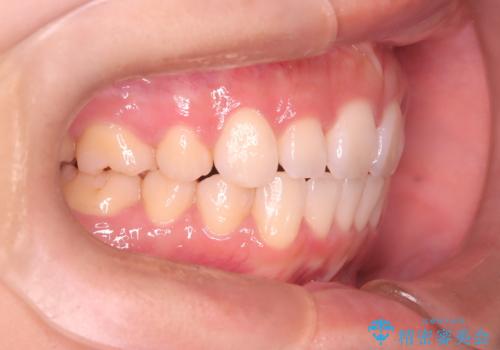

【審美装置】前歯のがたがたを治したい

- 前歯の凸凹と口元の突出感を主訴に来院されました。

臼歯関係が上顎前突傾向のため、上の小臼歯を抜歯してワイヤー矯正を行なっております。

下顎の叢生はIPRを行なって配列しています。